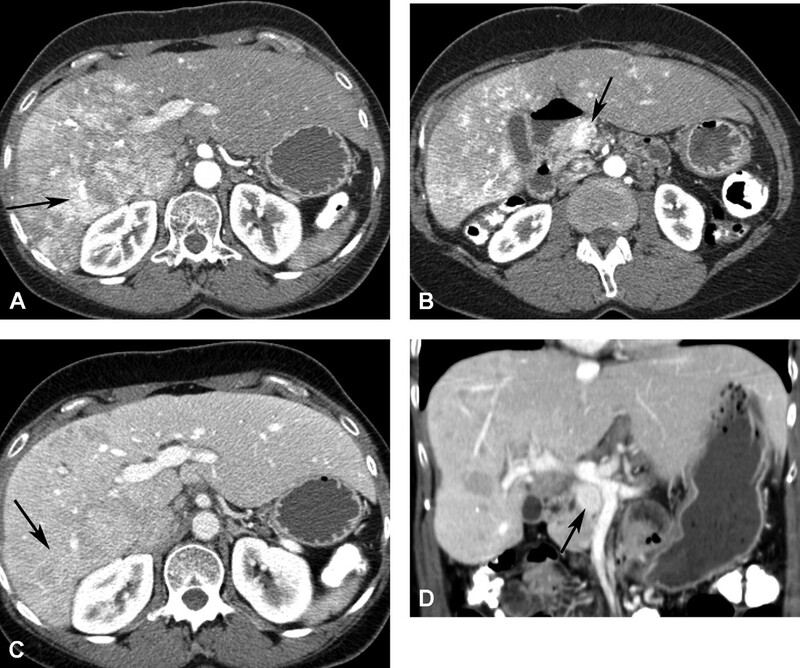

Di căn đến gan từ các u nguyên phát như u tế bào tiểu đảo/thần kinh nội tiết, carcinoid, carcinoma tế bào thận, melanoma và carcinoma tuyến giáp thuộc về nhóm di căn gan giàu mạch máu. Trên siêu âm di căn là các tổn thương giảm âm. Vùng trung tâm hoại tử có thể giảm âm hoặc echo trống. Hầu hết di căn giảm đậm độ trên CT không cản quang. Di căn của u thần kinh-nội tiết có thể tăng đậm độ trên CT không cản quang. Hầu hết các di căn giàu mạch máu bắt quang sớm mô u sống ở thì động mạch và giảm đậm độ với nhu mô gan ở thì tĩnh mạch cửa (Hình 14-18). T2W có tín hiệu thay đổi, thường tăng tín hiệu trung bình và giảm tín hiệu trên T1W, Melanoma là một ngoại lệ, ở đó tích tụ melanin, có tính chất rút ngắn thời gian T1, có thể dẫn đến tín hiệu cao trên T1W (Hình 19). Bắt Gd đặc trưng cho thấy tổn thương rõ rệt nhất ở thì động mạch với viền bắt thuốc ngoại vi điển hình (Hình 20C).

Hình 16. Nam 44 tuổi u tế bào tiểu đảo di căn gan đa ổ. CT thì động mạch (A) thấy các ổ di căn bắt quang không đồng nhất (mũi tên). U tế bào tiểu đảo (mũi tên ở B) ở đầu tụy bắt quang mạnh ở thì động mạch. Thì tĩnh mạch cửa (C) các tổn thương di căn thải thuốc (mũi tên). U tế bào tiểu đảo còn tăng đậm độ (mũi tên ở D) trong thì tĩnh mạch cửa.

Hình 17. U tế bào tiểu đảo di căn gan. Nhiều ổ di căn ấyở gan là các ổ giảm tín hiệu trên T1W (A) và tăng tín hiệu trên T2W (B). Ghi nhận khối lớn nhất cấp máu quá mức và gây hoại tử trung tâm có tín hiệu thấp trên T1W (A, mũi tên) và tín hiệu cao trên T2W (B, mũi tên). Tất cả các tổn thương bắt thuốc viền ngoại vi mạnh ở thì động mạch (C, tổn thương lớn nhất được đánh mũi tên), thải thuốc nhanh ở thì tĩnh mạch cửa (D, tổn thương lớn nhất được đánh mũi tên). Vùng trung tâm trong tổn thương lớn nhất (mũi tên ở E) nghèo mạch máu và không bắt thuốc ở thì động mạch, nhưng thường có thể tụ tập thuốc tương phản ở thì mô kẽ trễ.